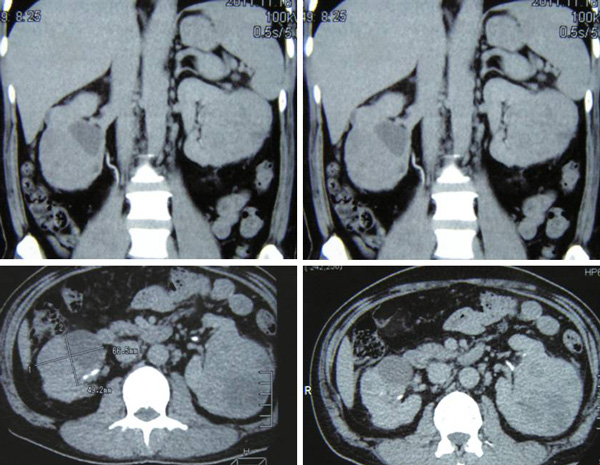

An ultrasound of his abdomen on 27 May 2011 indicated a 67.2 x 64.2 mm mass in his right kidney and a 70.5 x 56.0 mm mass in his left kidney.

A CT scan done on 16 November 2011 indicated a large mass, 6.7 x 8.4 x 7 cm in size in the left kidney. The right kidney has a nodular mass, 6.6. x 4.9 x 6.4 cm in size. Appearances are highly of bilateral renal neoplasm.